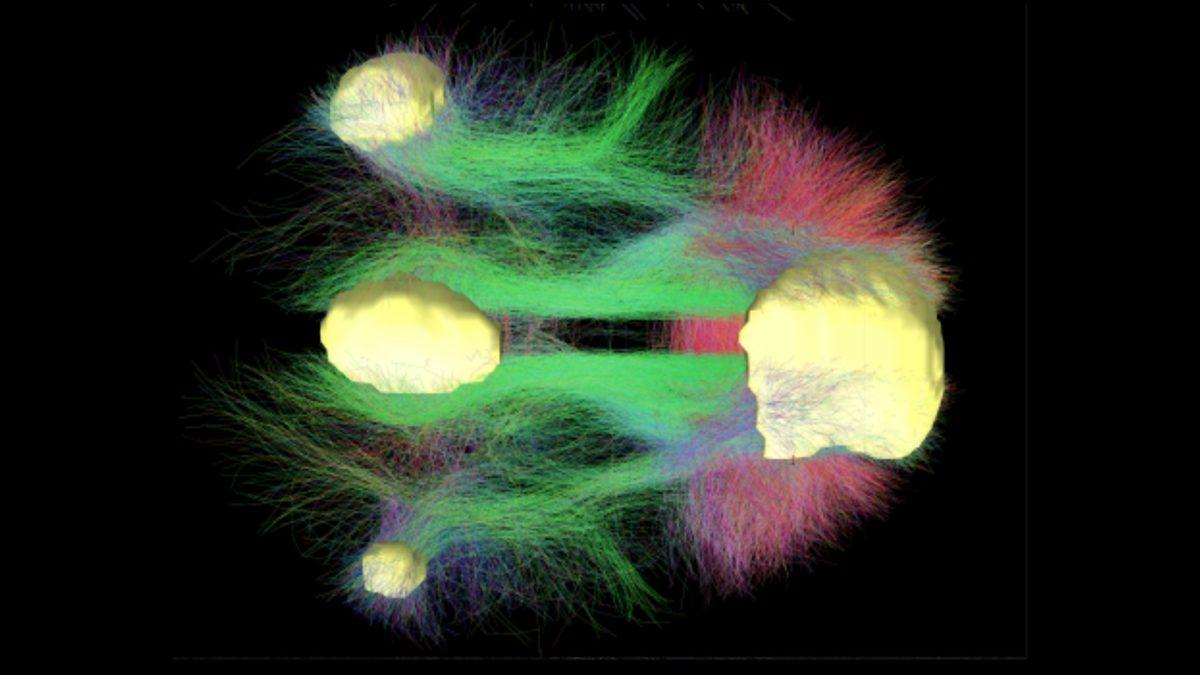

Bilim insanları, bu istemsiz dalıp gitmeyi bir hipotezle açıklıyor. Bu hipoteze göre, insan beyninde DMN (Default Mode Network) adı verilen bir ağ bulunuyor ve bu ağ, beynin diğer tüm bölgeleriyle etkileşime girdiğinde kişi, elinde olmadan uzaklara dalıp gitmelere başlıyor. Oldukça ilginç olan bu hipotezle ilgili detaylara ve daha fazlasına gelin, birlikte bakalım.

Bir kişi, çevresinde yaşanan şeylere karşı ilgisiz olduğunda veya tam odaklanmadığında, kişinin beyni uyanık bir dinlenme haline geçiyor. DMN denen bu ağ, insanlar geçmişlerini veya geleceklerini düşündüklerinde ve kendi içlerine kapanık bir hal aldıklarında da devreye girerek etkisini gösterebiliyor.